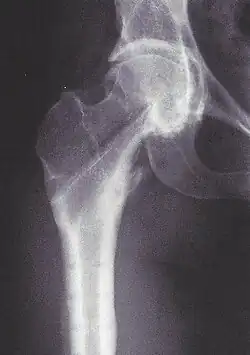

Coxa vara (lateinisch coxa ‚Hüfte‘, varus ‚auswärts gebogen‘) ist ein deskriptiver Begriff für eine nicht normale und nicht altersgemäße Stellung des oberen Endes vom Oberschenkelknochen. Der (schwer messbare) CCD-Winkel liegt unter 126°. Steht der Femurkopf unter dem Trochanter major (CCD < 90°), spricht man von einer Hirtenstabdeformität.

Röntgen

Zur Diagnose und Verlaufsbeurteilung reichen Röntgenaufnahmen. Bei der aussagekräftigen Beckenübersicht im Stand sollten die Füße geschlossen nebeneinander stehen; denn nur dann ist der Seitenvergleich des CCD-Winkels möglich. Die Rotation des Femurhalses ist am besten in der Computertomografie zu sehen. Der Femurkopf drängt zur Pfannenmitte. Diese sog. Zentrierung gefährdet den Boden des Acetabulums. Nur die intertrochantere Valgisierung kann (bei gesundem Knochen) die Protrusio acetabuli verhindern.[3] Diese Korrekturosteotomie ist viel seltener sinnvoll als die intertrochantere Varisierung.

Neben den angeborenen und erworbenen Formen werden (seit 1928) „extrem seltene“ Störungen der Ontogenese unterschieden. Bezeichnet werden sie als Developmental coxa vara, Infantile or cervical coxa vara oder Coxa vara infantum.[1][4] Sie entwickelt sich bei Kindern zwischen dem 3. und 7. Lebensjahr. Jungen und Mädchen sind gleichermaßen betroffen, in 30 % beiderseits.[1] Die Pathogenese ist unklar.[5] Charakteristisch ist das rechtwinklige obere Femurende mit einer weiten Epiphysenfuge. Obwohl sie senkrecht steht, ist der Femurkopf weder abgerutscht noch entrundet. Empfohlen wurde die Abduktionsosteotomie.[6]